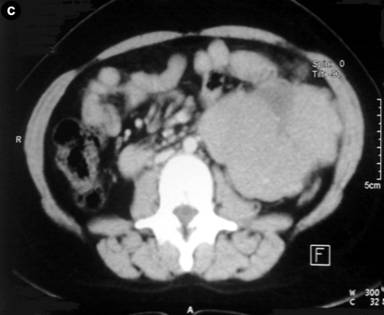

A 18-year old-female presented with progressively increasing mass in the left hypochondrium and epigastric regions of 6 months duration. There was no history of jaundice, vomiting, change in stool color, diarrhea, or flushing. On examination there was a painless, firm mass occupying the epigastric, left hypochondrium, umbilical regions which did not move with respiration. Laboratory investigations were normal, with normal serum level of CEA. Imaging in the form of ultrasonography revealed a large complex mass in the left retroperitoneum measuring 17x22x7 cm. Contrast enhanced multislice CT scan showed a large well defined mass of 17x24 cm with areas of degeneration, involving the region of the body and tail of pancreas, extending upward to the retrogastric space and downward to the level of aortic bifurcation, with no evidence of metastasis, with criteria suggestive for a solid and cystic papillary neoplasm of the pancreas (Figure 1).

Figure 1. Abdominal CT scan shows a large, well-demarcated, heterogeneous pancreatic mass. |